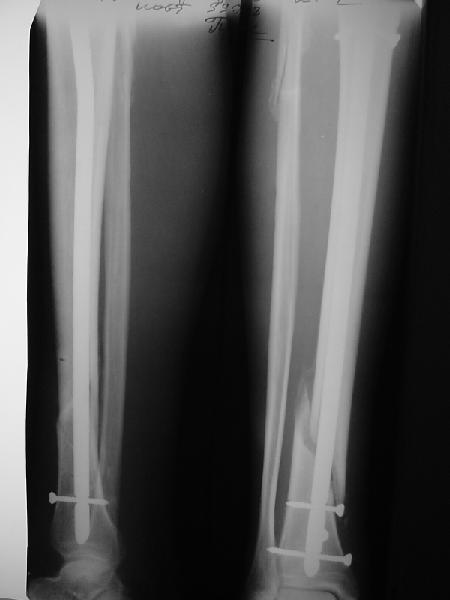

На мой взгляд, на снимках, приведённых Вами - неправильно сростающийся перелом дистальной трети большеберцовой кости, состояние после остеосинтеза интрамедуллярным гвоздём.

Как Вы пишите снимок под номером 1 - менсяц после операции, под номером 2- два месяца после операции.

Вы не послали послеоперационный снимок, поэтому трудно судить о состоянии редукции после операции.

Позвольте по поводу техники операции высказать своё мнение...

Установка с медиальной стороны гвоздя в области дистального фрагмента дополнительного шурупа помогло бы Вам репонировать и удержать перелом в анатомическом положении, предотвратило варусную деформацию и смещение по ширине.

Кстати, если можно пошлите послеоперационный снимок.

На мой взгляд внутрикостная фиксация переломов дистальной и проксимальной трети большеберцовой кости, за исключением поперечных, не очень хорошее решение вопроса, аппарат Илизарова или Тэйлора, позволяющие призвести закрытую анатомическую редукцию и отличное удержание отломков в период сращения.

Пример, приведённый Вами в нашей дискуссии по времени нагрузки после остеосинтеза не совсем удачный... Ваш больной имеет счастье, что первым согнулся проксимальный замыкающий винт, а не дистальный и гвоздь не пенетрировал голеностопный сустав.